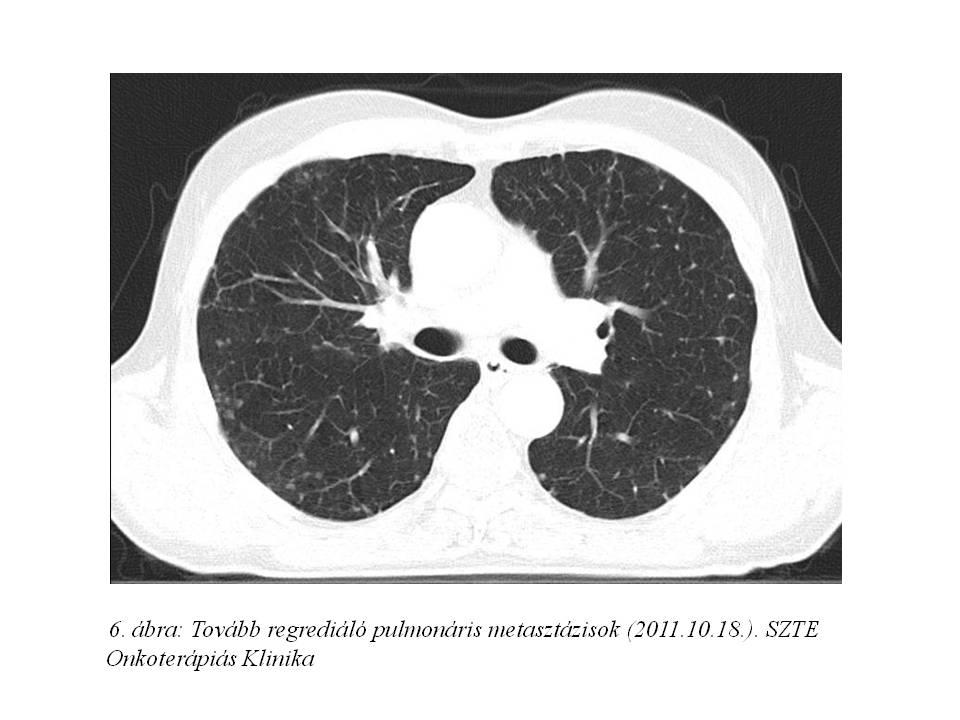

A screening során a beteg staging-jét mellkas CT vizsgálattal egészítettük ki, mely a korábban készült mellkasi röngenvizsgálaton észlelt multiplex tüdőmetasztázisok jelenlétét megerősítette.

Palliatív onkológiai kezelésként FOLFIRI-bevacizumab immunochemotherápia indult 2011.07.05-től. Az első re-stagingkor (3. ábra, 4. ábra) már parciális remissziót észleltünk (46% csökkenés) mind a primer tumor, mind a tüdő-, mind a máj metasztázisok méretében. 2011.10.18-ára (5. ábra, 6. ábra) a regresszió tovább nőtt (59%). A kezelés mellékhatásaként, az irinotecan infúziót követően jelentkező orrváladékozást (irinotecan okozta specifikus parasympatikus tünet) a további kezelések során sc. atropinnal premedikáltuk, míg Gr.I. postinfúziós vénagyulladását lokálisan kezeltük. A 30. ciklustól a kezeléseket követően émelygés jelentkezett, mely otthon szedett ondansetron hatására megszűnt. Az 53. ciklust követően Gr.III-as hasmenés, exsiccatio és Gr.IV. neutropénia miatt hospitalizálás vált szükségessé. Empirikusan indított intravénás, széles spektrumú, kombinált antibiotikum, sc. filgrastim kezelés, parenterális folyadék-, és elektrolit pótlás hatására állapota rendeződött. Kezelését ezt követően folytattuk, de az észlelt súlyos mellékhatások miatt 25%-os redukciót alkalmaztunk a kemoterápiás szerek dózisában.